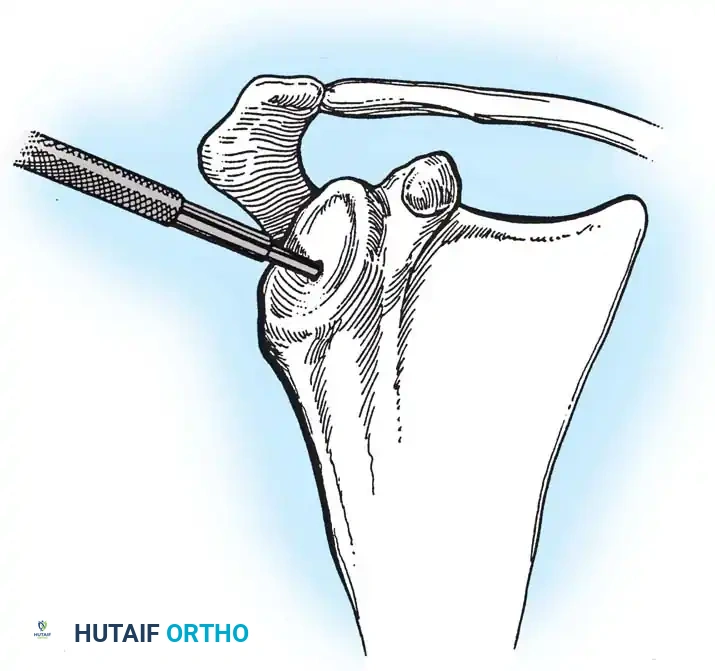

4. Glenoid Preparation

Excellent exposure is critical. Release the inferior capsule completely from the glenoid rim.

* Identify the center point of the glenoid.

* Perform concentric reaming to correct version and create a bleeding bone bed.

* Pitfall: Avoid excessive reaming, which penetrates the dense subchondral bone plate and enters the weaker cancellous vault, leading to catastrophic early subsidence.

Cement the all-polyethylene glenoid component using pulsatile lavage, meticulous drying, and pressurization techniques.